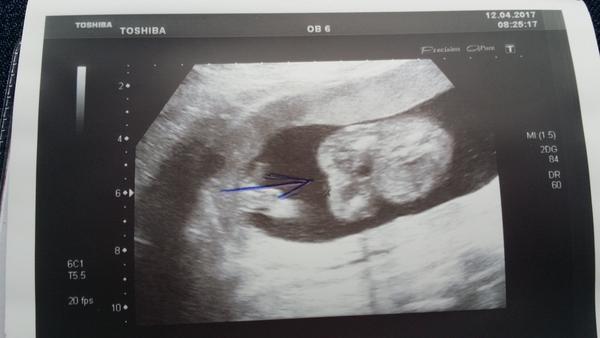

Ahoj maminky a budoucí maminky 😉 Prosím, poradila byste mi některá, co vidíte na fotce z ultrazvuku ve 20. týdnu za pohlaví? Určitě jste foteček viděly už mraky, proto vás žádám o radu...Nechci nikoho ovlivnit, proto svůj tip řeknu později 🙂 Děkuju moc!!!

Ahoj, bohužel jediné co vidím, je sladké malé miminko, ale pohlaví z této fotky určit nelze. Taky je dost brzy, ale já jsem kolem toho 14 tt pindíka zahlídla 🙂 Tohle zatím vypadá na holčičku, ale to je opravdu jen tím, že není nic jako pinďa přímo vidět!

@sophien mám tu stejnou fotku, moje je holčička. Ale na tvé fotce vidím nějaký canfrňour...😕 tak nevím no...

@sophien Právě no. Já bych se u tebe teda přikláněla spíš ke klučinovi 🙂. Dr ti řekla holku?

@novamamina Právě holku, no, prý podle pohlavních valů🙂